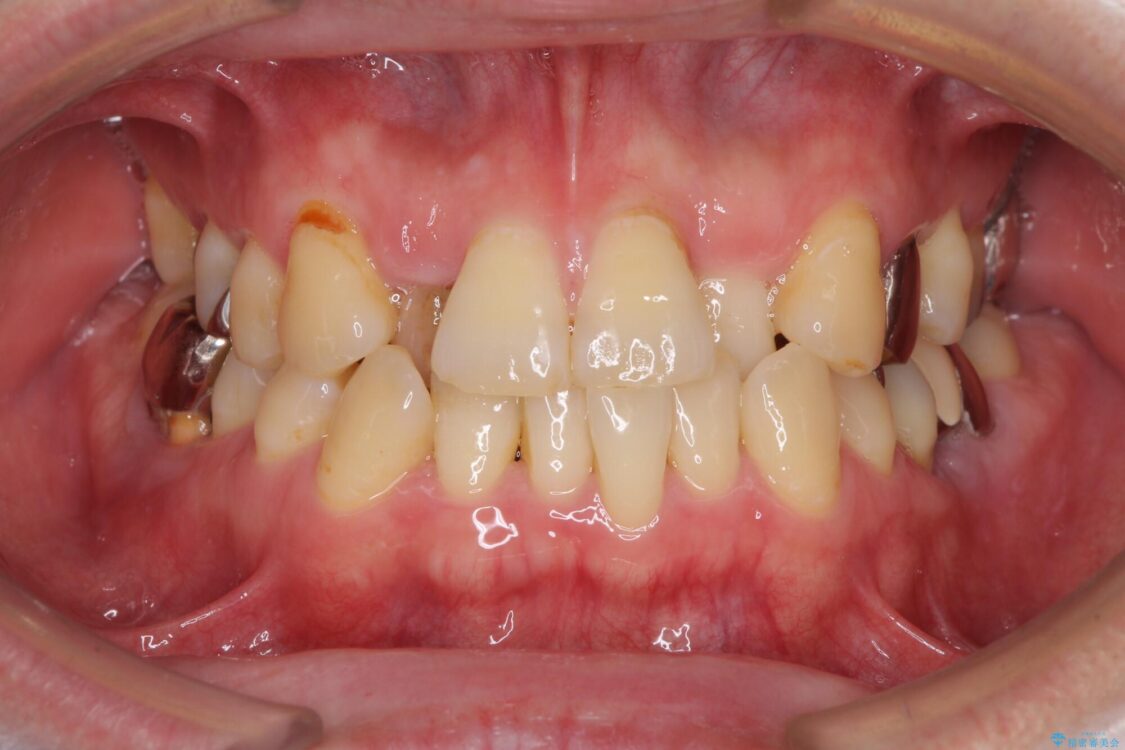

奥歯の痛みと前歯のデコボコを気にして来院された患者様です。

左右下顎の大臼歯は、ともに歯根が破折しており、抜歯が必要な状態でした。

放置したことで炎症による骨吸収が顕著であるため、骨造成を併用してインプラント埋入を行うこととしました。

咬み合わせは受け口傾向であり、上顎前歯の叢生が顕著であったことから、第1小臼歯抜歯による矯正治療も検討しましたが、下顎大臼歯を左右ともに抜歯するため、非抜歯による矯正治療を行うこととしました。

治療前